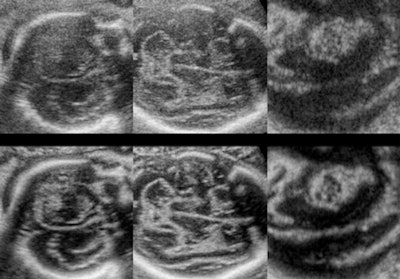

For example, 3D fetal ultrasound examinations have demonstrated a superior visualization of subtle fetal brain defects and other fetal anomalies after 3D image enhancement has been applied to the 3D volume. Specifically, structures in the near field behind the skull bone are better visualized in the fetal brain with 3D, according to Dr. Anders Selbing, PhD.1

![]() |

| Fetal brain: Upper row contains nonprocessed 3D-acquired images in A, B, and C planes. Lower row contains enhanced 3D-acquired images in A, B, and C planes. Note the structures in the near field behind the skull bone are becoming visible, leading to new diagnostic possibilities. Images courtesy of Dr. Anders Selbing, PhD.1 |